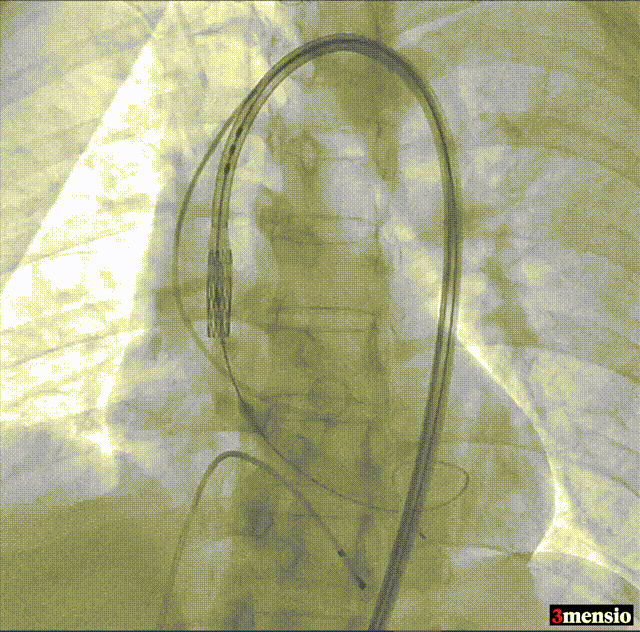

3.通过支撑导丝,送入SAPIEN 3瓣膜,使用独特调弯功能,保证安全过弓并成功跨瓣。

4.调整至共平面角度,瓣膜到位,180次/min快速起搏下精准释放26mm SAPIEN 3瓣膜。

5.瓣膜植入且撤出导丝后,造影及超声结果均显示瓣膜工作良好,无残余瓣周漏,瓣膜植入成功。